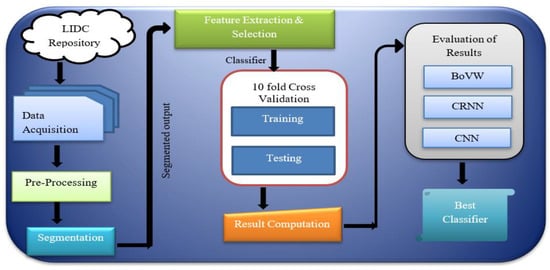

According to WHO (World Health Organization), 8.9 million deaths occur due to lung cancer worldwide, and in 2030 the number is estimated to reach 17 million [6]. The only option to reduce the fatality rate is early screening and diagnosis. The quintessential part needed is lung tissue segmentation for quantitative analysis of CT images and computer-aided diagnosis. As the development of new devices in this era is evolving, we need fast, accurate, and mostly automatic lung cancer diagnosis, which is much more important than impractical methods [7]. Computer-Assisted Diagnosis (CAD) is a computerised study of medical images currently in use. It is commonly used to identify and treat medical imaging anomalies. CAD has become significant in identifying pulmonary nodules using radiology CT images. The CAD software helps radiologists to have a second opinion in affirming their decision in distinguishing the abnormalities, the evaluation of disease improvement, and the differential conclusion of the disease [8]. Figure 1 shows the block diagram of the proposed cancer detection method.

Figure 1.

Block diagram of the cancer detection method.

In the proposed solution in this research, the first step was running image pre-processing for identifying particles. That was briefly done via intensity measurement. Afterwards, the pre-processed image was segmented using a standard segmentation technique followed by extraction and selection of features. Some texture features were extracted during feature extraction using the Approximate Bayesian Computation (ABC) parameter, the GLCM method, and the Factor of Safety (FOS) parameter. It was then followed by the classification process, which includes benign and malignant tumors, considering the CT scanned images. A few extracted features were used to train the classifier. The corresponding trained classification model was created with the model evaluation and obtained improved detection and classification accuracy, specificity, and sensitivity. Figure 2 shows the basic framework for the proposed system.

Figure 2.

Framework for the detection of Lung cancer for a CAD System [28].